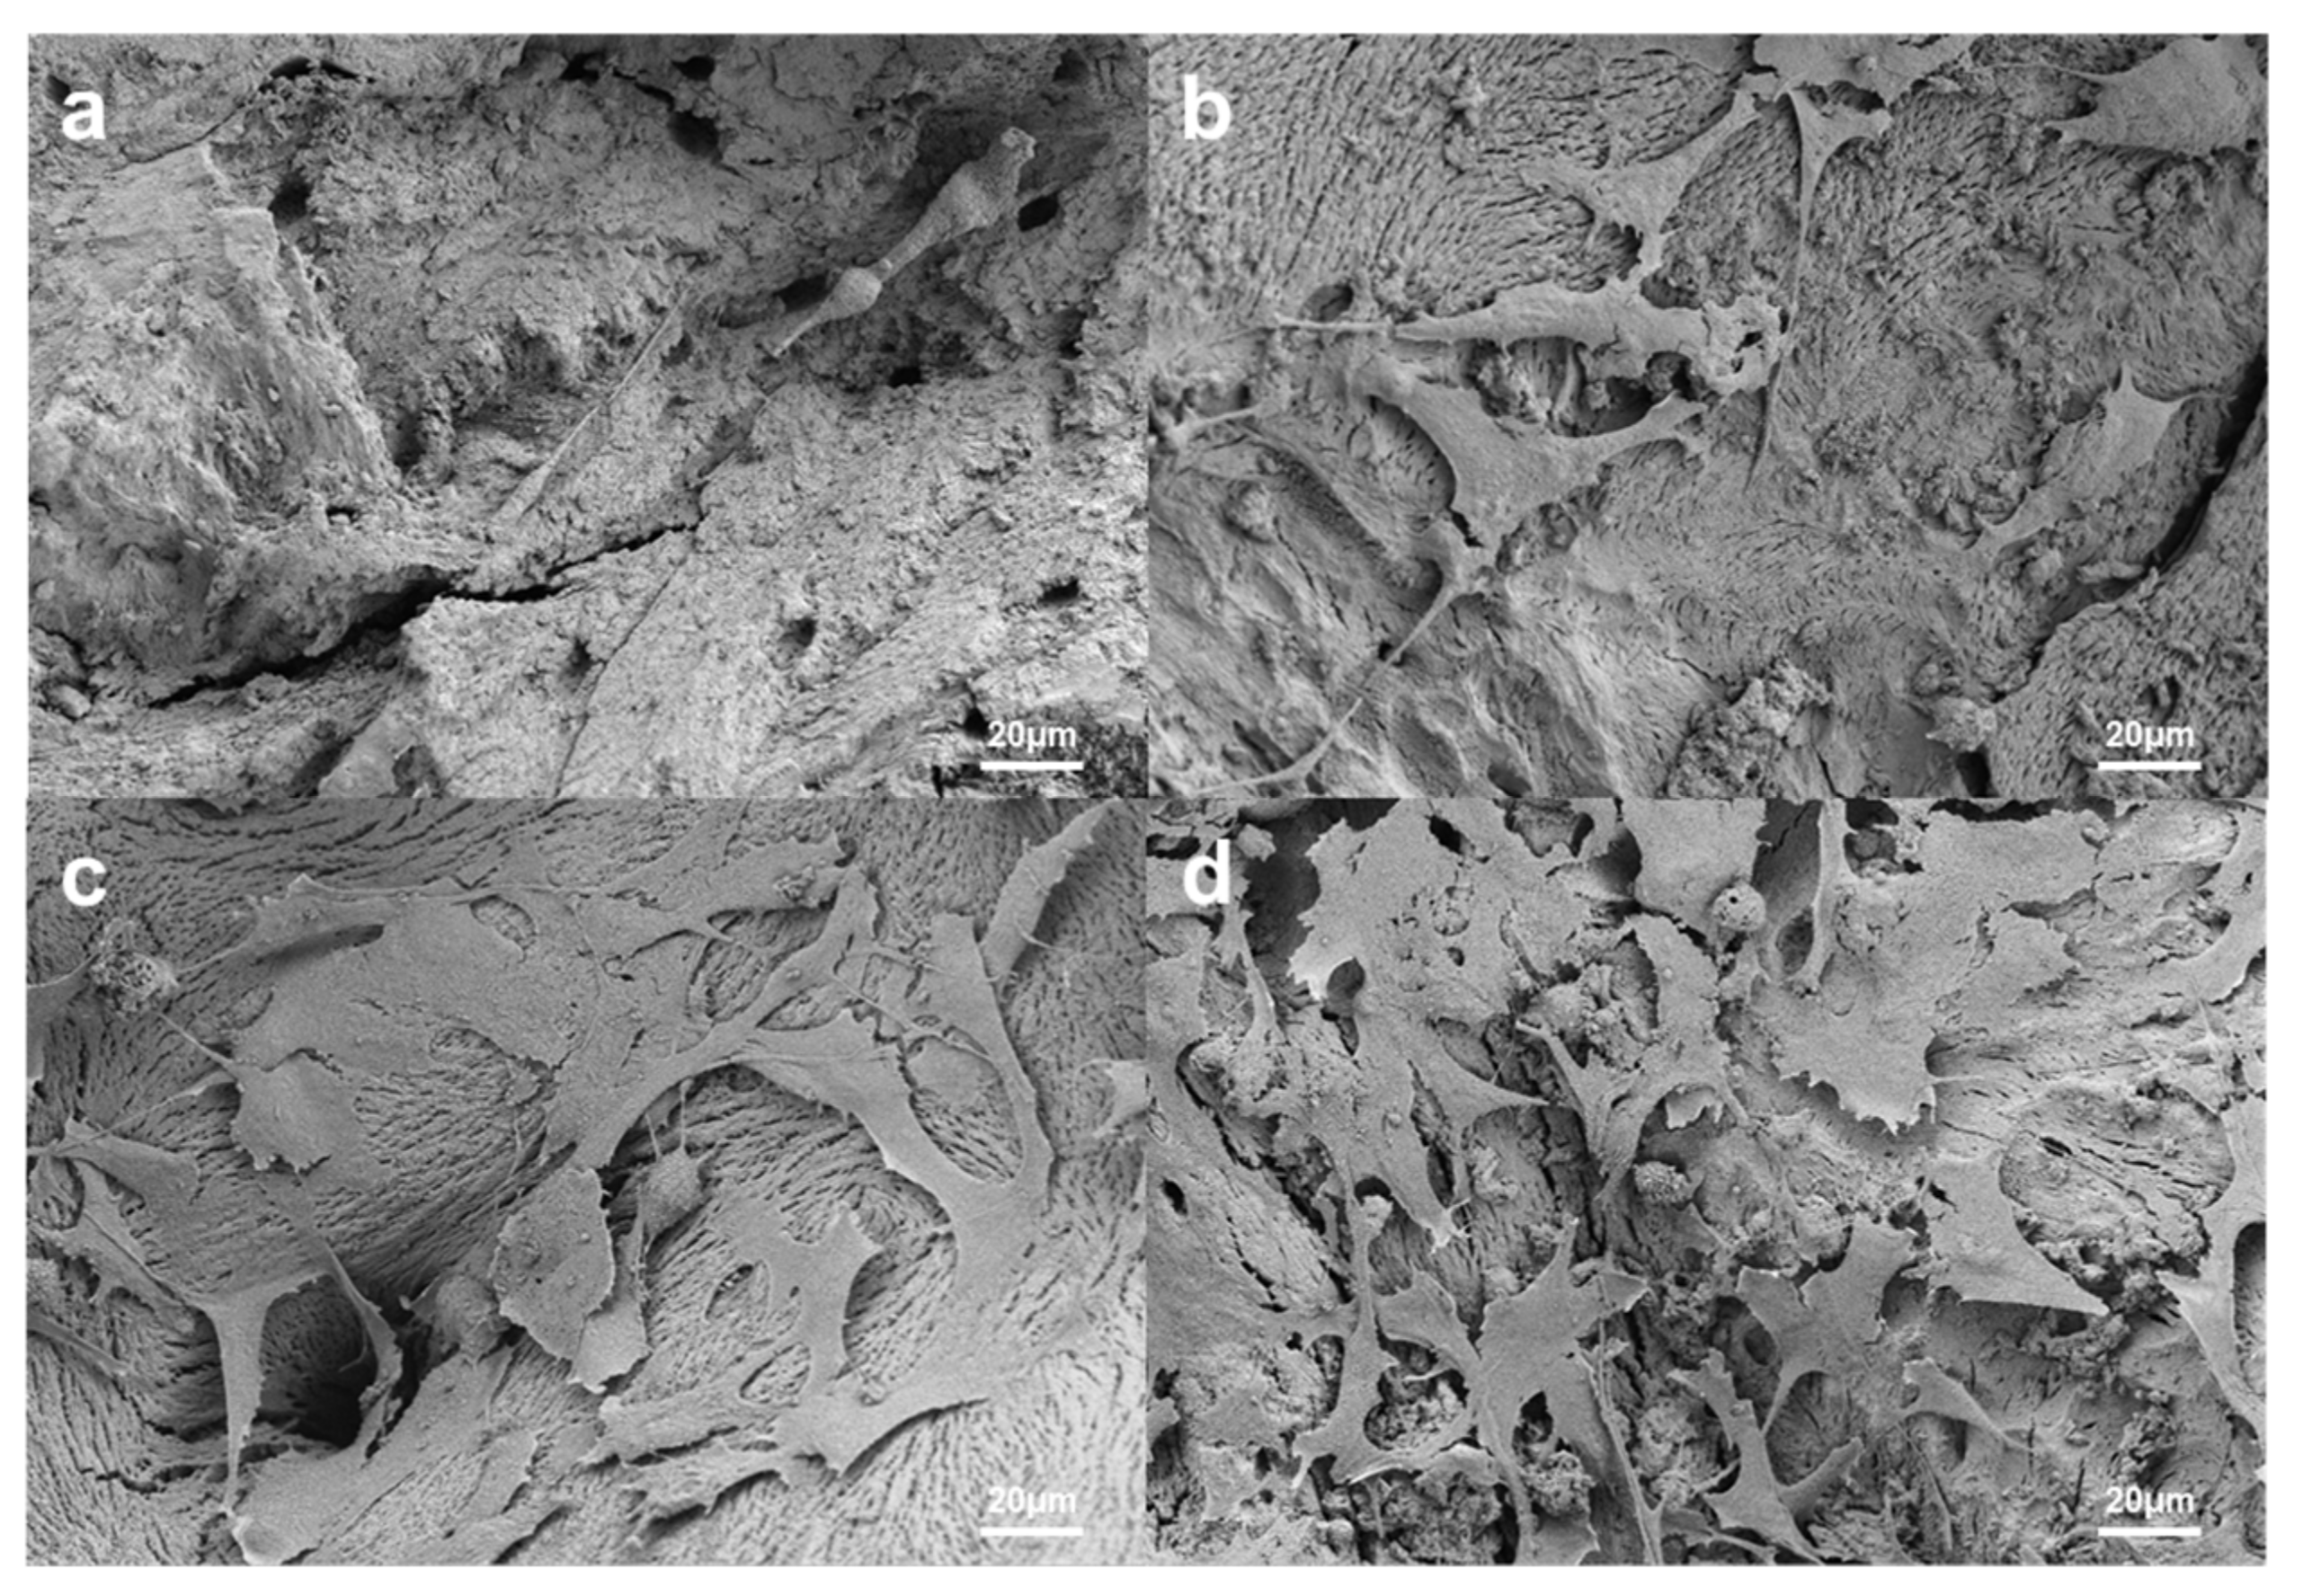

3.1.1. Scanning Electron Microscope Surface Analysis

3.1.4. Cell Attachment